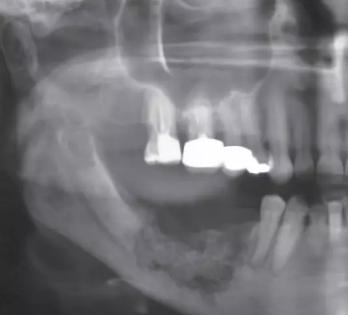

牙 双膦酸盐相关性颌骨坏死(BRONJ)作为使用BPs药物引起的严重不良反应,由口腔科医生Marx2003年首次报道。。根据2009年美国口腔颌面外科医师协会(AAOMS)确立的BRONJ诊断标准,可定义BRONJ为:口腔颌面部存在8周未愈合的骨面暴露,且患者正在接受或接受过BPs药物治疗但无头颈部放疗史。该病发病率虽低,但由于严重的临床表现,并且尚无有效根治方法,近年来受到越来越多学者的关注。(图4)

牙 双膦酸盐相关性颌骨坏死的发病机制较复杂,目前学者通过研究提出了数种假说。其中较受关注的是,口腔外科操作导致颌骨创伤后,双膦酸盐通过抑制破骨细胞活性,抑制颌骨表面溶骨性活动,诱导破骨细胞凋亡,间接抑制成骨细胞的骨质沉积作用,使骨重建速度减慢,增加下颌骨坏死风险。值得注意的是,根据现有的文献报道,BRONJ只发生在颌骨,尚未发生在其他骨。(图5 6)

牙 BRONJ的临床表现与放射性颌骨坏死类似,患者可能长期无明显症状,也可表现为颌骨疼痛或骨面裸露。典型的临床表现包括疼痛、骨面裸露、软组织肿胀、感染、牙齿松动、溢脓、瘘管形成。也可见骨面暴露但不伴感染症状的病例。其他症状还包括牙关紧闭、口臭、复发性脓肿、上颌窦炎、口腔上颌窦瘘等。当压迫周围神经时,可出现剧烈的颌骨疼痛或麻木,病情严重者甚至出现病理性骨折。